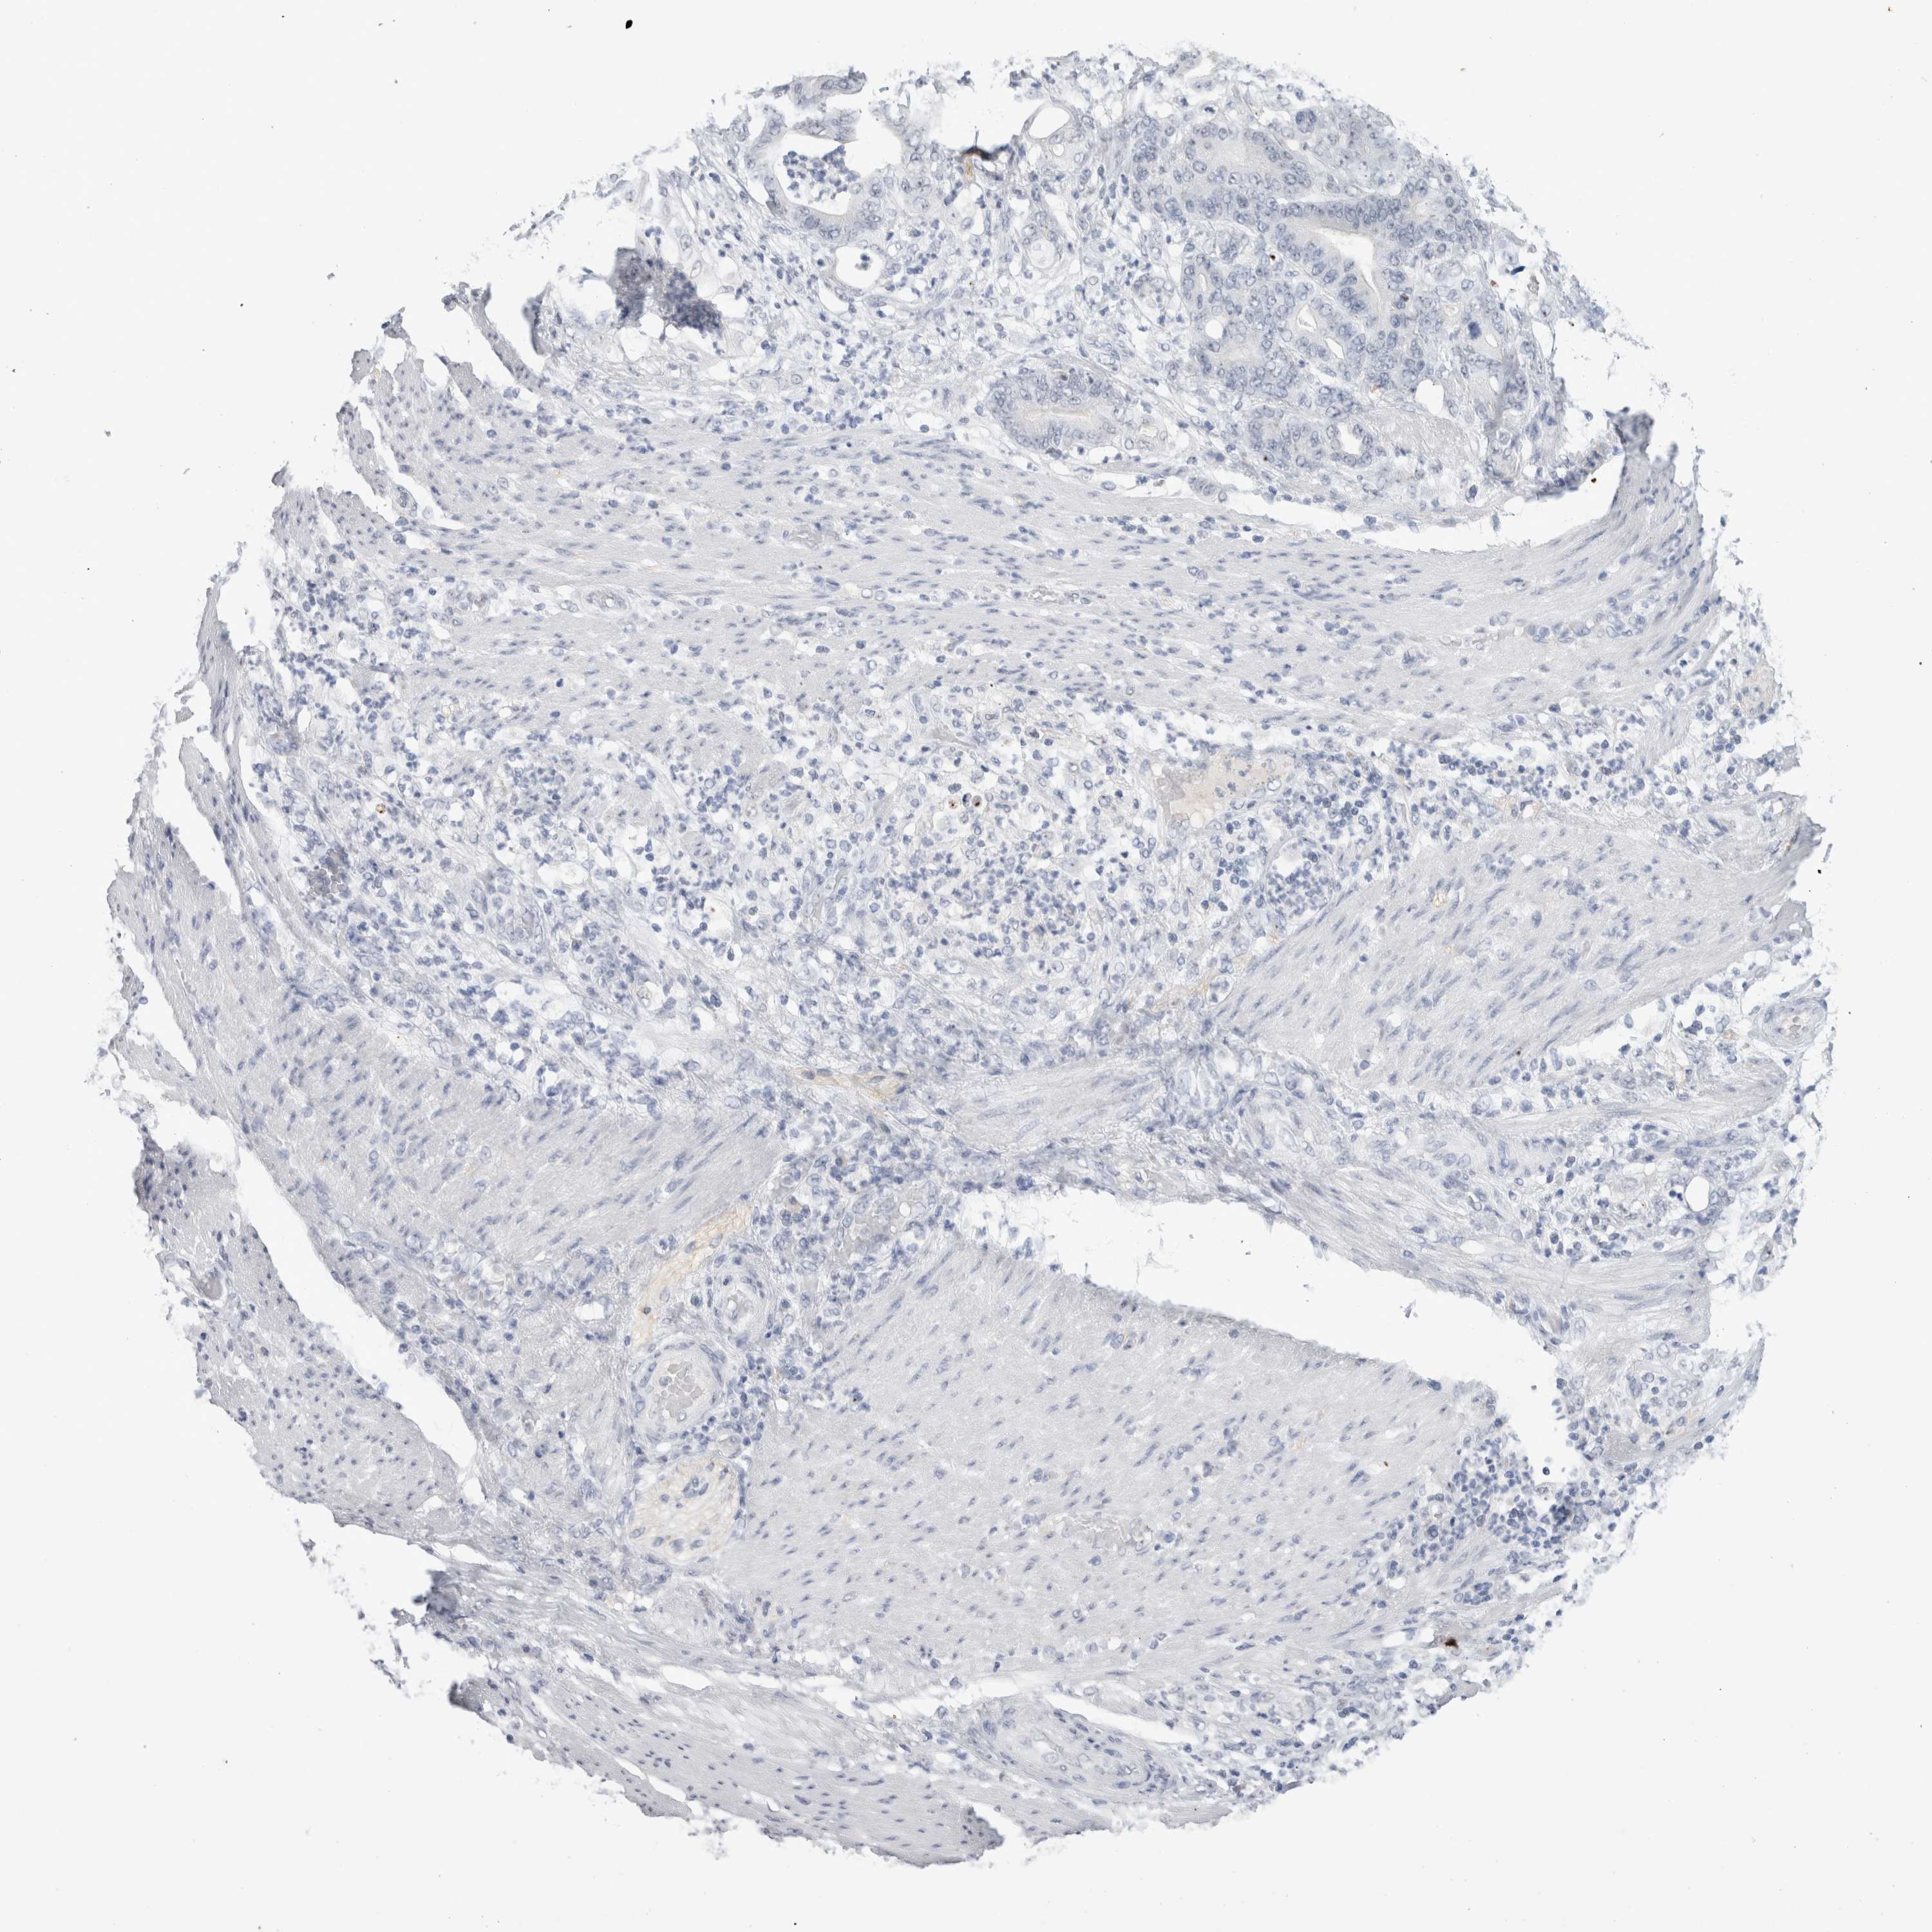

STOMACH CANCER - Protein expressioni

A mouse-over function shows sample information and annotation data. Click on an image to view it in a full screen mode. Samples can be filtered based on level of antibody staining by selecting one or several of the following categories: high, medium, low and not detected. The assay and annotation is described here.

Note that samples used for immunohistochemistry by the Human Protein Atlas do not correspond to samples in the TCGA dataset.

Antibody stainingi

Antibody staining in the annotated cell types in the current human tissue is reported as not detected, low, medium, or high, based on conventional immunohistochemistry profiling in selected tissues. This score is based on the combination of the staining intensity and fraction of stained cells.

Each image is clickable and will lead to virtual microscopy that enables deeper exploration of all samples and also displays staining intensity scores, fraction scores and subcellular localization as well as patient and tissue information for each sample.

Antibody HPA002981

Antibody CAB025746

Staining

High

Medium

Low

Not detected

Adenocarcinoma, NOS

Adenocarcinoma, High grade